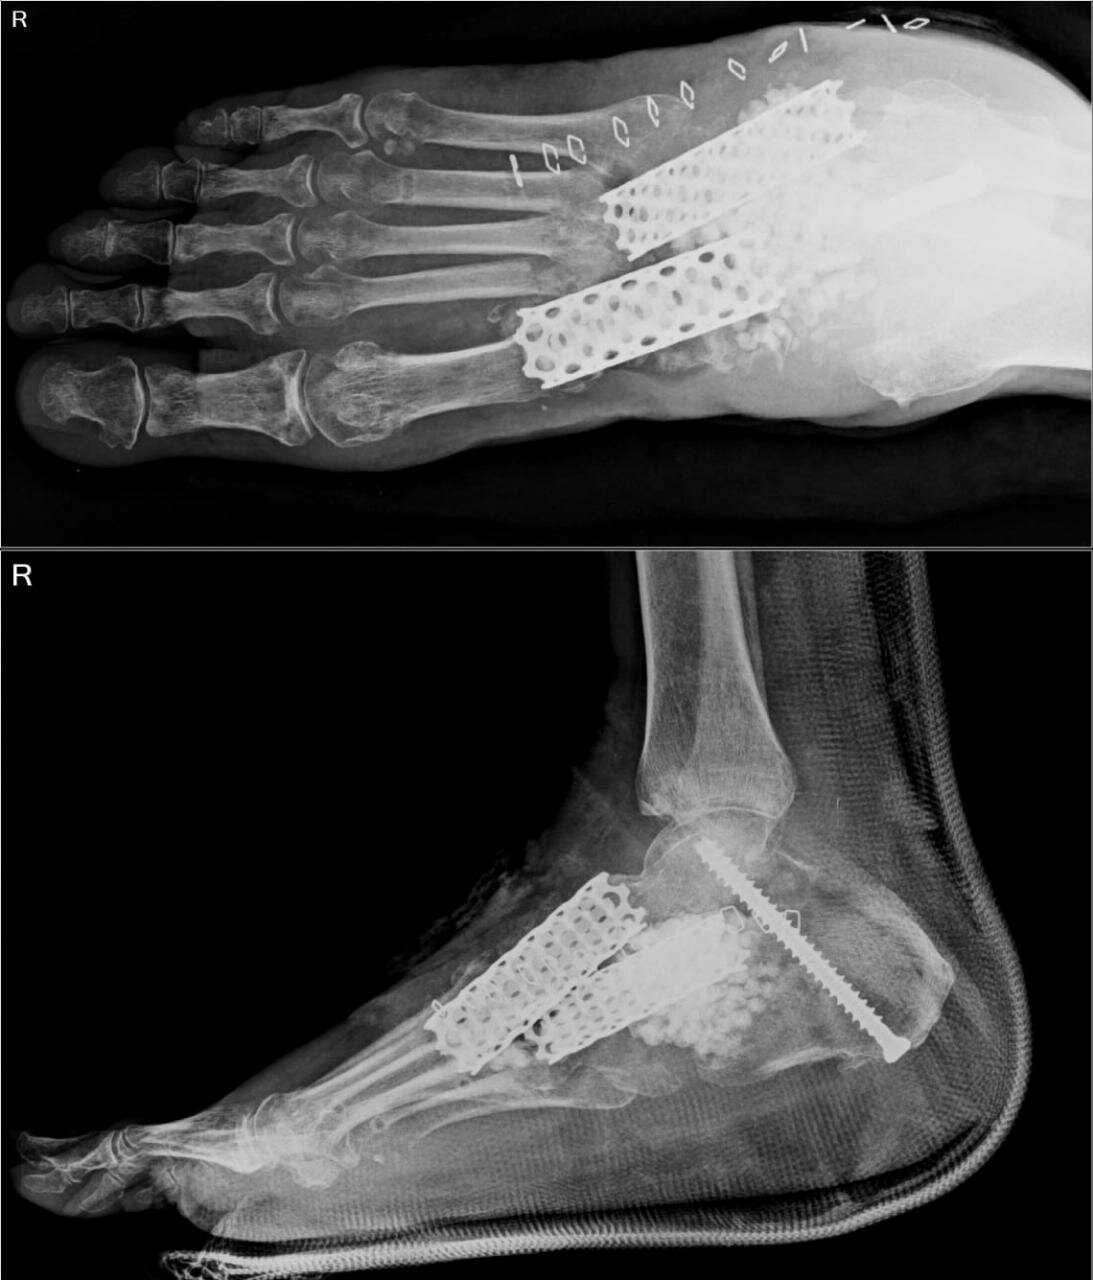

Use of metallic cage for Midfoot & hindfoot bone defect - first time in India

Titanium cylindrical surgical mesh cages have been developed for use in spine surgery as intervertebral spacers and for vertebral defect replacemen...